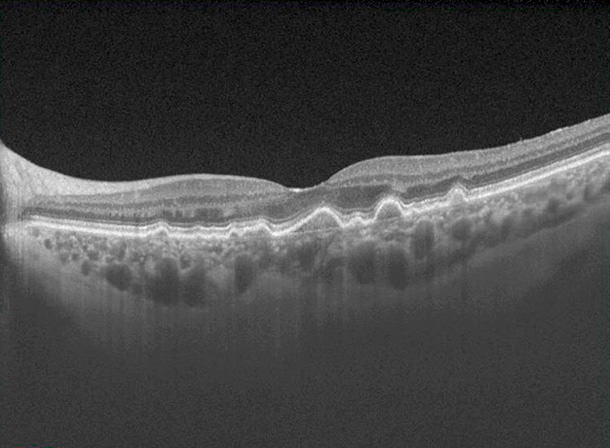

La DMAE afecta la parte central de la retina, donde se encuentra la visión central y se produce la fijación. Su conservación tiene un alto valor, ya que nos permite llevar a cabo actividades diarias y simples como leer, ver la televisión o conducir sin dificultad. Sus síntomas más comunes son experimentar visión central borrosa, o percibir una mancha en el campo visual.

También llamada DMAE seca. Es aquel tipo de DMAE sin líquido dentro de la retina. La pérdida es más lenta, pero al igual que la DMAE húmeda es también irreversible.

- Es importante iniciar el tratamiento antes de que la atrofia haya afectado la parte central de la mácula

Se ha detectado que las drusas, que son unos depósitos que aparecen debajo de la retina en pacientes con formas iniciales de DMAE, están llenas de proteínas del sistema del complemento. También se ha detectado que mutaciones genéticas en este sistema del complemento se han asociado con un riesgo mayor de desarrollar DMAE. De ahí la convicción de que el sistema inmune participa, aunque solo sea en parte, en la génesis de la DMAE.